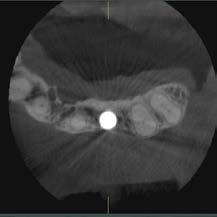

Der Patient stellte sich nach dem Einsetzen eines Implantats im Bereich des lateralen Schneidezahns oben links zu einer routinemäßigen Nachuntersuchung vor. Das Implantat war 3 Monate zuvor eingesetzt worden. Auf koronaler, sagittaler und axialer Ebene war ein großer, runder, gut definierter, glatter Bereich mit geringer Dichte im Zusammenhang mit der apikalen Ansicht des Implantats zu erkennen. Die hochauflösenden Bilder zeigen, dass die bukkale Kortikalis fehlt und bestätigen daher die schlechte Prognose aufgrund der vorhandenen Periimplantitis.